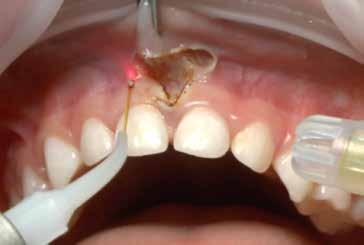

S.V. Paziente di tre anni di sesso maschile, in III Classe scheletrica lieve, con open-bite, deglutizione atipica, contrazione dell’arcata superiore, tendenza alla III Classe. Alla prima visita il paziente presentava un evidente frenulo vestibolare corto, a tetto labiale che, trazionando il labbro superiore, tendeva a ischemizzarsi insieme alla papilla retroincisiva.

In situazioni simili si potrebbe anche attendere ma, poiché si rendeva necessaria una terapia ortodontica, si è proceduto ad eseguire una frenulectomia e il giorno stesso è stato consegnato al paziente l’apparecchio elastodontico per la correzione della malocclusione. Lo scudo vestibolare dell’apparecchio ha contribuito alla guarigione del frenulo stesso determinando una trazione continua sul labbro superiore.

La sequenza terapeutica ha previsto i seguenti step:

• frenulectomia laser;

• terapia elastodontica al fine di ripristinare la corretta crescita scheletrica e dentale.

Fig. 4

Fig. 5 > Immagine intraorale frontale.

Fig. 6 > Immagine intraorale laterale destra.

Fig. 7 > Immagine intraorale laterale sinistra.

Fig. 8 > Dettaglio del frenulo labiale superiore corto.

Figg. 9-11 > Intervento di frenulectomia con laser a diodo.

Figg. 12, 13 > Controllo dopo ventiquattro ore.